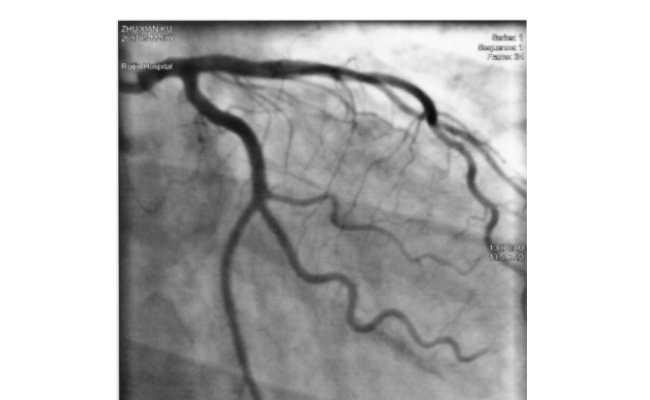

血管造影導(dǎo)管

導(dǎo)管介入技術(shù)在現(xiàn)代醫(yī)學(xué)中扮演著重要的角色,而血管造影導(dǎo)管作為其中的關(guān)鍵部分,在臨床上被廣泛應(yīng)用。那么,下面一起來了解下血管造影導(dǎo)管的特性及構(gòu)造?一、血管造影導(dǎo)管的主要特性1、彈性和柔韌性:通常由柔軟的材料制成,如聚乙烯或硅膠,導(dǎo)管能夠在血管系統(tǒng)中彎曲和穿過狹窄的血管,達(dá)到需要檢查或治療的部位。2、兼...

國產(chǎn)冠脈球囊有哪些

在當(dāng)前醫(yī)療領(lǐng)域,冠脈球囊應(yīng)用非常廣泛,國產(chǎn)冠脈球囊有哪些成為了患者及醫(yī)生關(guān)心的問題。與進(jìn)口產(chǎn)品相比,國產(chǎn)技術(shù)在近些年有了顯著的提高,成為了眾多專家和醫(yī)生討論的焦點。1.技術(shù)原理解析當(dāng)我們談及國產(chǎn)冠脈球囊時,要明確它的工作原理。冠脈球囊是通過導(dǎo)管進(jìn)入人體冠脈狹窄部位,通過充氣使之?dāng)U張,從而達(dá)到恢復(fù)冠脈...